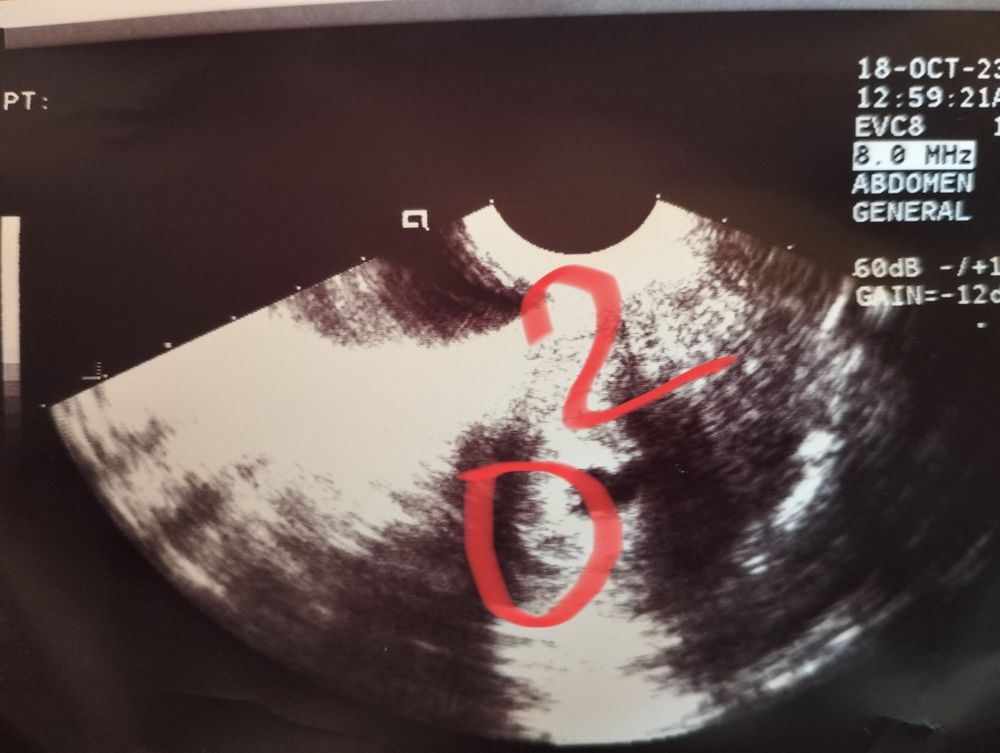

Был один малыш,а теперь двойня

Изображение Изображение Sabedoria,ну если смотреть по сниму то их двое в одном месте,хотя может срок маленький ещё и ничего толком не ясно🥰

Алина Петрова, я не совсем поняла где первый, а где второй?это первый? Изображение А второй вы обвели?